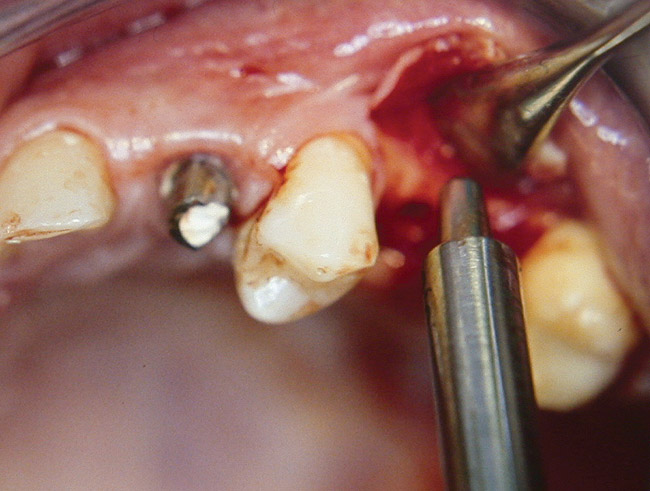

At the time of surgery, local infiltrative anesthesia was administered (lidocaine 2% with epinephrine, 1:100,000). A full-thickness mucoperiosteal flap was raised. The initial osteotomy was performed on midcrestal bone using a rose-headed bur. To prepare the osteotomy site for implant placement, sequential alternating osteotomes with variable conicity were used, drilling 2-mm shorter than the length of the implant to be placed (Figure 3A and Figure 3B). The implants presented initial primary stability (Figure 4), the cover screws were placed, and the implants were submerged for a healing period. The tissue was approximated, and the patient was instructed not to wear any denture or to place pressure on the healing site.

Figure 3a  Alternating osteotomes with variable conicity used to perform the alveolar remodeling in the area of tooth No. 24.

Figure 3a

Figure 3b  Alternating osteotomes with variable conicity used to perform the alveolar remodeling in the area of tooth No. 24.

Figure 3b